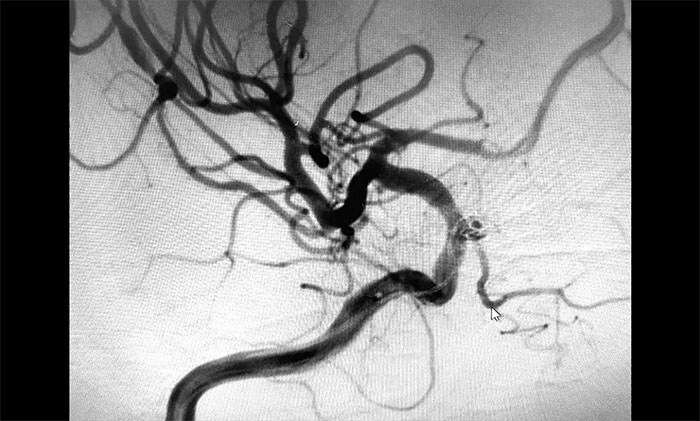

▲栓塞后,载瘤动脉血流通畅

术中,在微导丝的引导下将微导管头端小心送入动脉瘤腔内,之后顺着这个通路往动脉瘤内填塞弹簧圈,造影显示动脉瘤瘤内造影剂明显滞留,眼动脉(载瘤动脉)血流通畅。遂解脱弹簧圈并释放支架,再次造影,支架覆盖动脉瘤,贴壁良好。整台手术历时90分钟顺利完成,患者术后恢复情况良好。